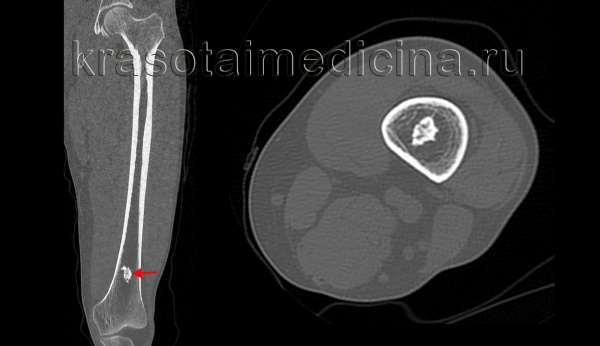

Крупная остеохондрома проксимальной части малоберцовой кости: рентгенограмма (а), трехмерная КТ-реконструкция (б), КТ-срез (в). Образования этой локализации могут стать причиной нейропатии малоберцового нерва.

В данном случае имеется выраженная вогнутая деформация прилежащего кортикального слоя большеберцовой кости, являющаяся примером вторичной деформации кости вследствие экспансивного роста остеохондромы. Остеохондрома на ножке дистального отдела бедра. Образования обычно растут в противоположную от суставов сторону. Спонгиозная часть остеохондромы сообщается с костно-мозговым каналом пораженной кости. Образование сохраняет единство кортикального и спонгиозного слоя с материнской костью, что является рентгенологическим признаком остеохондромы. Остеохондрома на широком основании дистального конца большеберцовой кости. Обратите внимание на угловую деформацию пилона большеберцовой кости. Образования подобной локализации могут приводить к нарушению роста и угловой деформации костей. Множественный остеохондроматоз, сопровождающийся деформацией костей. Это наследственное заболевание с аутосомно-доминантным типом наследования. Пациент с симптоматикой, обусловленной компрессией большеберцового нерва. Рентгенограмма коленного сустава пациента с множественными остеохондромами. Имеются множественные поражения дистального отдела бедра и проксимального отдела большеберцовой кости и сопутствующая деформация конечности. Интраоперационная картина остеохондромы. Обратите внимание на непрерывность кортикального слоя и «шапку», образованную зрелой хрящевой тканью. Микропрепарат остеохондромы. Гистологически эти образования выглядят также, как зоны роста костей — хрящевая ткань, созревающая путем энхондрального окостенения и превращающаяся в нормальную костную ткань. Макропрепарат остеохондромы. Обратите внимание на хрящевую «шапку» с сохранением непрерывности костно-мозгового пространства остеохондромы и пораженной кости.